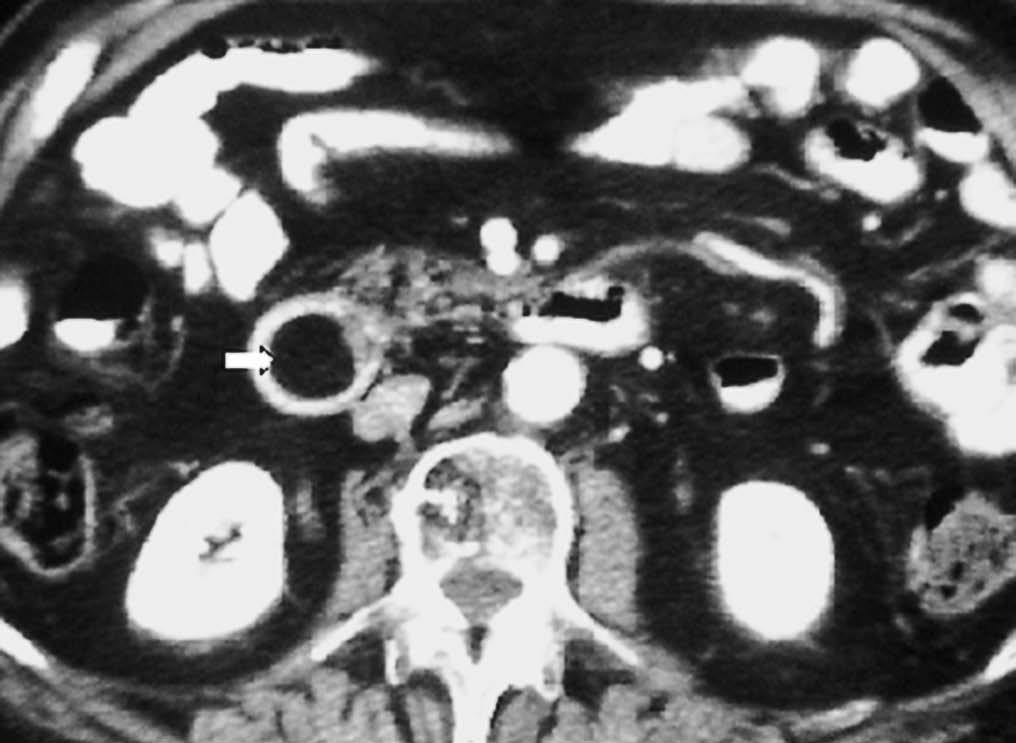

El duodeno es una localización infrecuente de diverticulitis. La imagen radiológica consiste en un engrosamiento de la pared del duodeno asociado a un divertículo, en ocasiones con un enterolito en su interior, con inflamación de la grasa adyacente16 (fig. 9).

Fig. 9--Diverticulitis duodenal. (A) En la ecografía se observa un divertículo (flechas) con engrosamiento de pared duodenal (D) y alteración de la grasa adyacente (*). (B) Tomografía computarizada de otro paciente con inflamación de divertículo duodenal. Se oberva una lesión quística (punta de flecha) de pared gruesa y borrosa, con material en su interior. P: Páncreas.